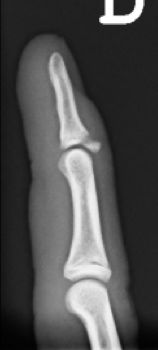

Se trata de una deformidad del dedo con flexo de la falange distal por lesión del tendón extensor o un arrancamiento óseo en la base de la tercera falange. Es más frecuente en la adolescencia, aunque puede ocurrir a cualquier edad. El dedo en martillo tendinoso por rotura del extensor sin lesión ósea se trata con una férula con la IFD en extensión durante 8 semanas. Se debe realizar un tratamiento quirúrgico cuando existe fractura con un fragmento avulsionado superior al 40% de la superficie articular pudiendo realizar diferentes técnicas quirúrgicas. (Figura 19)

Figura 19: a, b- Fractura de la falange distal desplazada con avulsión tendón extensor. Tratamiento quirúrgico mediante técnica de Ishiguro